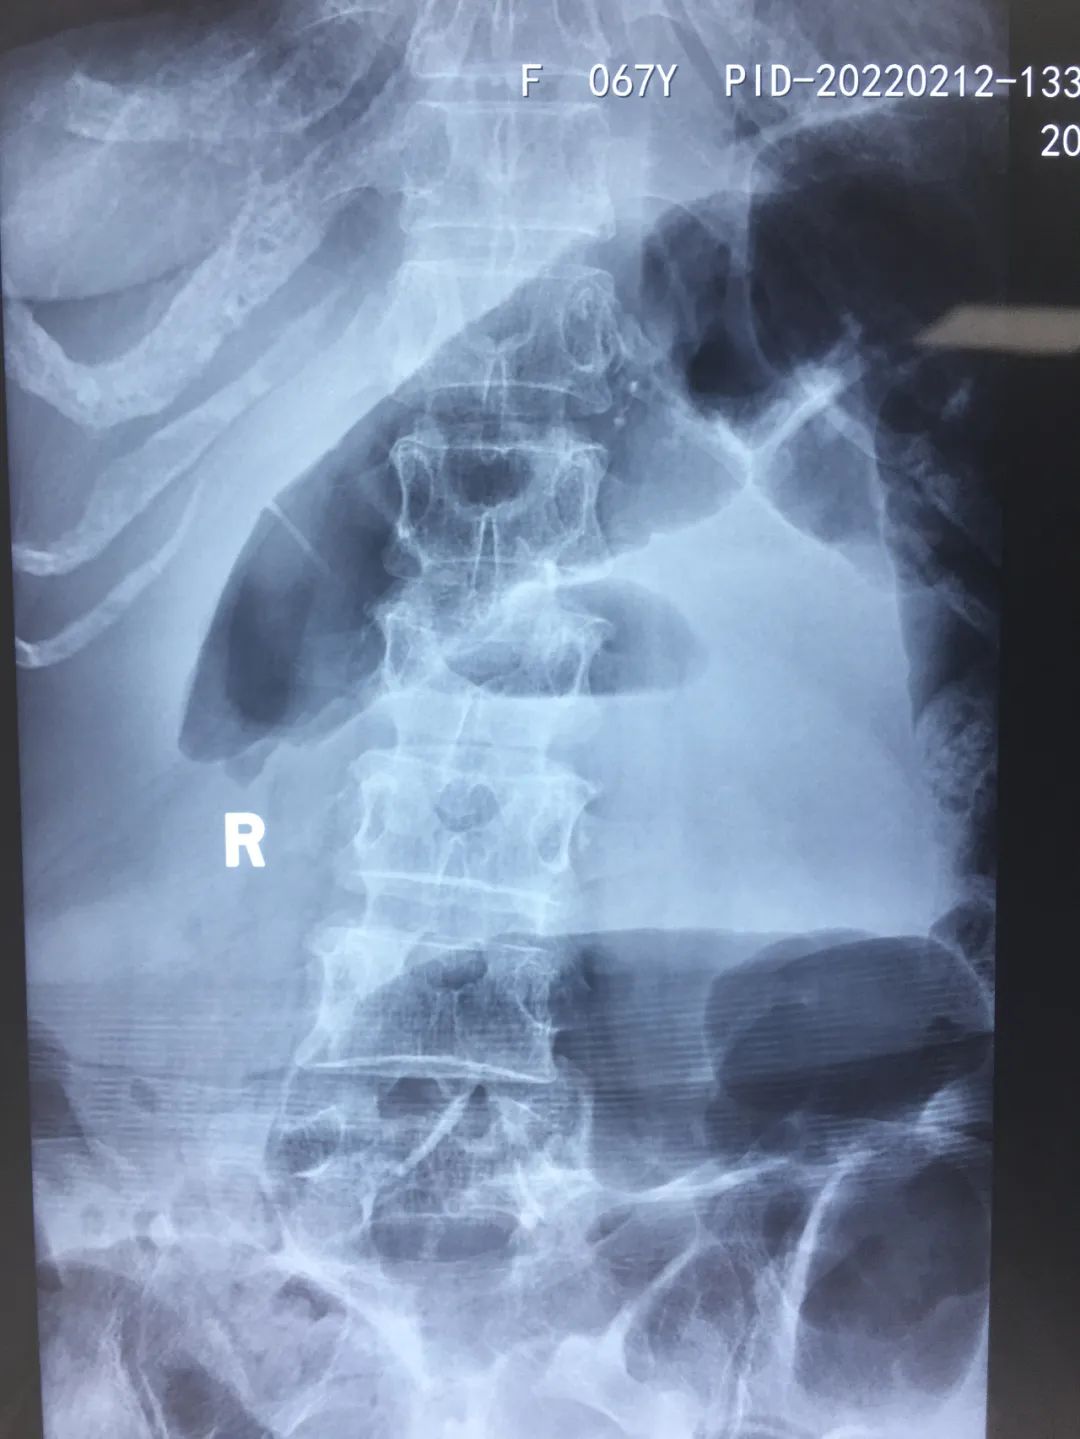

2月12日,家人将她送到陕西冶金医院就诊。医生完善相关检查,拍片提示:腰2椎体新近压缩性骨折,遂收住骨科。

检查中发现王阿姨腰2椎体新近压缩性骨折,右下腹肠管积气,麻痹性肠梗阻,特邀外科会诊。结合王阿姨情况,立即制定最佳手术治疗方案。